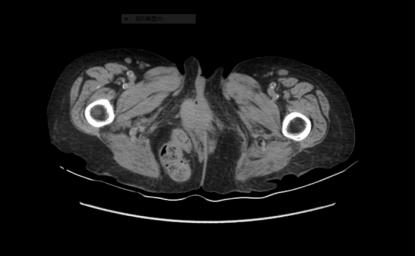

腹腔脏器经闭孔向股三角区突出的腹外疝称为闭孔疝。闭孔疝较罕见,在所有腹外疝中低于 0.07%。闭孔疝一般发生在消瘦、有多次生产史的老年女性患者中,因此在文献中又被称为「小老太太疝」。

闭孔是盆腔通至大腿的孔道,由耻骨支与坐骨支结合而围成的一对卵圆形大孔。闭孔为闭孔膜封闭,但留有一细管,管内有神经和血管通过。

闭孔疝位于耻骨肌的深层,股三角区的下端,在闭孔肌的上方,耻骨肌和内收长肌之间。

患者表现为大腿内侧疼痛,屈曲位可缓解,过伸、内收或内旋时疼痛加重。由于难以触及疝肿块,缺乏像其他腹壁疝(例如腹股沟疝)一样的特异性症状和典型包块,且大多数外科医生接诊此类患者经验较少,因此,闭孔疝的术前确诊往往比较困难,多为术中确诊。

Howship-Romberg 征(HR)是闭孔疝早期且最具特征性的征象,亦是术前做出确诊的主要依据,尤其年老体弱妇女有肠梗阻表现和 HR 征时,应考虑本病。但 HR 特异性不高,患者出现 HR 征时并不意味着一定都是闭孔疝,确诊闭孔疝的患者也并不一定都出现 HR 征。